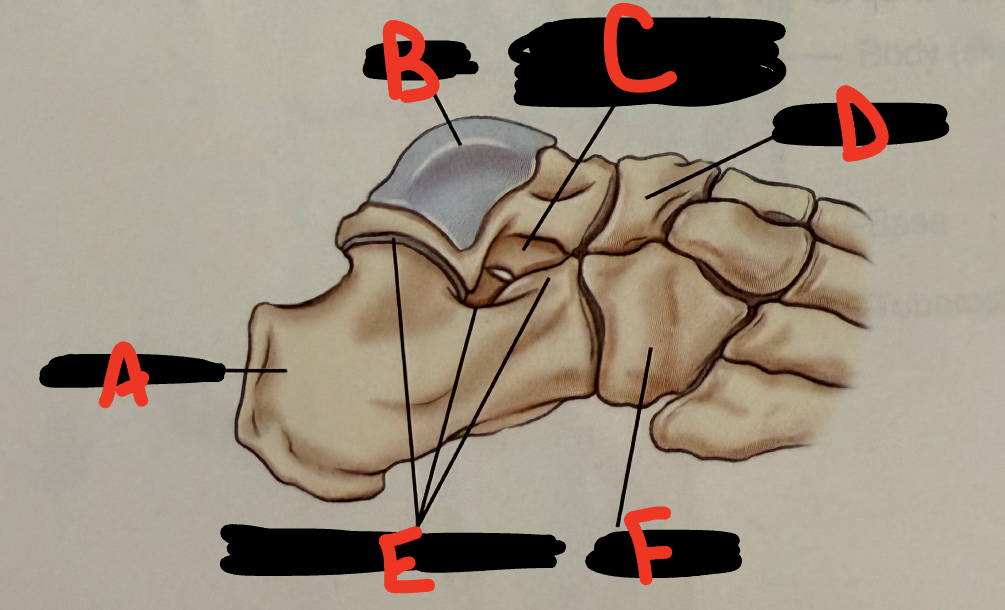

<p>A</p>

A

calcaneus

New cards

<p>B</p>

B

45

<p>C</p>

sinus tarsi

46

D

navicular

47

<p>E</p>

E

talocalcaneal joint

<p>F</p>

F